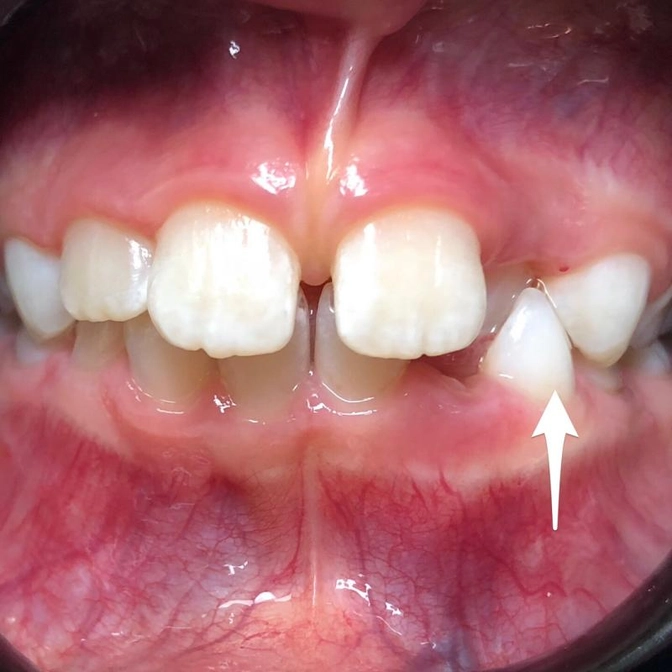

☝Все внимание на нижний клык

Указала на него стрелкой для наглядности

Он молочный

Поменяется позже

Примерно в 10-11 лет (это если брать во внимание средние сроки смены молочных зубов)

Но вот какая история: он собою «заслоняет» верхний боковой резец

А он уже постоянный.

Его перекрыл клык снизу.

Получился замок, который теперь раскрыться самостоятельно вряд ли сможет.